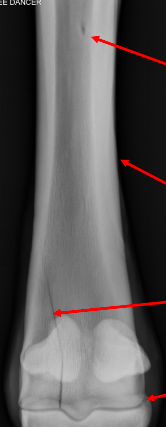

use the red arrows to label the bone from top to bottom

A

• epiphysis

• physis

• metaphysis

• diaphysis